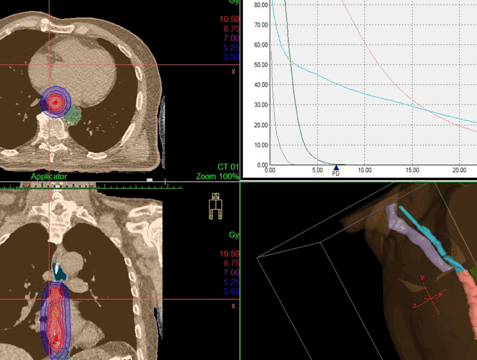

При невозможности операции единственный выход — облучение с химиотерапией.

При 4 стадии основной метод воздействия — химиотерапия. При выраженной дисфагии до химиотерапии стентом или лазером восстанавливают проходимость пищевода. При плохом самочувствии ограничиваются активной симптоматической терапией.

• Мультипланарная реконструкция изображений облегчает определение протяженности опухоли в краниокаудальном направлении, что необходимо для планирования хирургического вмешательства или лучевой терапии

Лучевая терапия

Применяется ионизирующее излучение с целью уничтожения клеток новообразования. Такая терапия может проводиться:

- Тем пациентам, которым по состоянию здоровья нельзя делать операцию. В этом случае облучение, обычно вместе с химиотерапией, представляет собой основную методику лечения.

- При локализации опухоли в области шейного отдела пищевода химиолучевая терапия является первым этапом комбинированного метода лечения.

- Перед операцией вместе с химиотерапией. Это нужно, чтобы уменьшить опухоль и обеспечить ее лучшее удаление (называется «неоадъювантная терапия»).

- После хирургического вмешательства вместе с химиотерапией. Таким образом воздействуют на остаточную опухоль, которую нельзя было увидеть во время операции (носит название «адъювантная терапия»).

- Для облегчения симптоматики при распространенном раке пищевода. Позволяет снизить интенсивность болевого синдрома, устранить кровотечение и трудности с глотанием. В данном случае это паллиативная терапия.

Разновидности лучевого лечения:

- Наружное (дистанционное). Источник ионизирующего излучения находится на расстоянии от пациента.

- Контактное (называется «брахитерапия»). Источник излучения эндоскопическим методом размещается как можно ближе к новообразованию. Ионизирующие лучи проходят малое расстояние, поэтому достигают опухоли, но мало затрагивают расположенные рядом ткани. Лечение позволяет уменьшить новообразование и восстановить проходимость.

Дозное распределение, получаемое при дистанционной конформной лучевой терапии и внутрипросветной брахитерапии